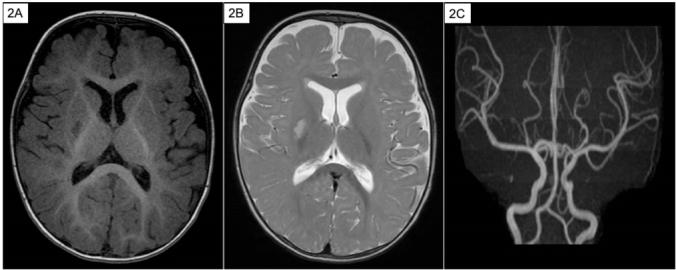

Ishaemic stroke (IS) in the paediatric population is extremely rare. In this age group, the occurrence of IS often concurs with underlying congenital heart disease, haematological, metabolic or immunological conditions. In contrast, the association between IS and minor head injury in children has been sparse in current literature. The authors report a case of a healthy 9-month-old male who was found to have a right middle cerebral artery territory infarct after a minor head injury. An extensive medical workup was performed, and it was negative for any previously undiagnosed co-morbidities. Given the paucity of such cases, the condition and its management are discussed in corroboration with current literature.

缺血性中风(IS)在儿科人群中极为罕见。在这个年龄组中,IS的发生常常与潜在的先天性心脏病、血液学、代谢或免疫性疾病同时出现。相比之下,目前文献中关于儿童IS与轻度头部损伤之间的关联很少。作者报告了一例健康的9个月大男性病例,该患儿在轻度头部损伤后被发现右侧大脑中动脉区域梗死。进行了全面的医学检查,未发现任何先前未诊断出的合并症。鉴于此类病例较少,结合当前文献对该病症及其治疗进行了讨论。